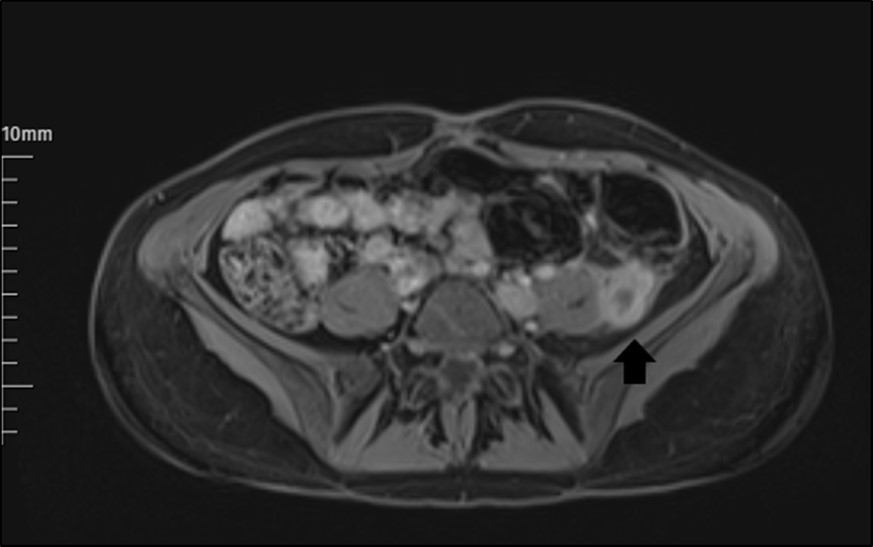

The abdomen and pelvis area were examined by MRI with contrast. It revealed a markedly dilated LOV containing abnormal soft tissue attenuation material throughout, indicating ovarian vein thrombosis. The aspect of a LOV in MRI images was persistent, with signs of increased signal in this area (Figure 1). Subsequent inferior abdominal MRI demonstrated a thrombus starting from the LOV to the level of the left renal vein. There is an enhancement in the vein walls (thrombophlebitis).

Figure 1.The appearance of a left ovarian vein in MRI.